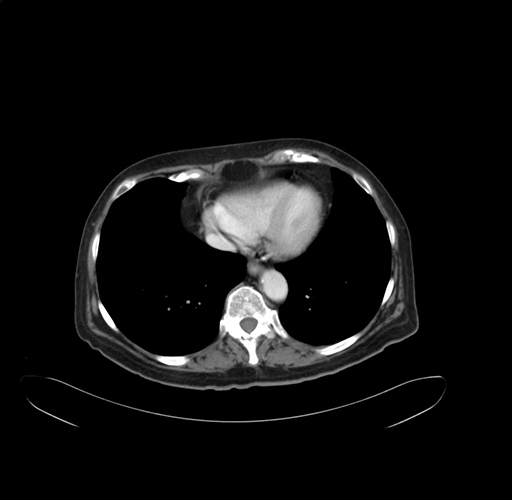

Pre-Chemo: Axial Venous

Axial Venous